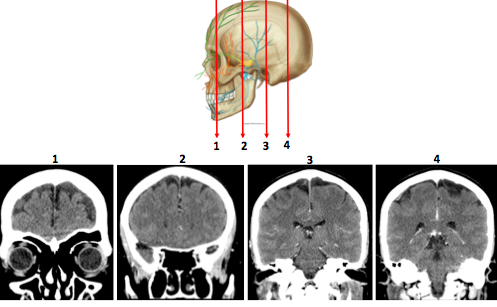

What can help determine the level of a cross section in neuroimaging?

What key anatomical features help distinguish the plane of the section?

What lobes are shown?

What level is this scan at?

What fissure can be seen?

1) Frontal lobe

2) R temporal lobe

3) Occipital lobe

Fissure –> Sylvian or lateral fissure

Level of the scan must be at the level of the eyebrow region as the two frontal sinuses are shown.